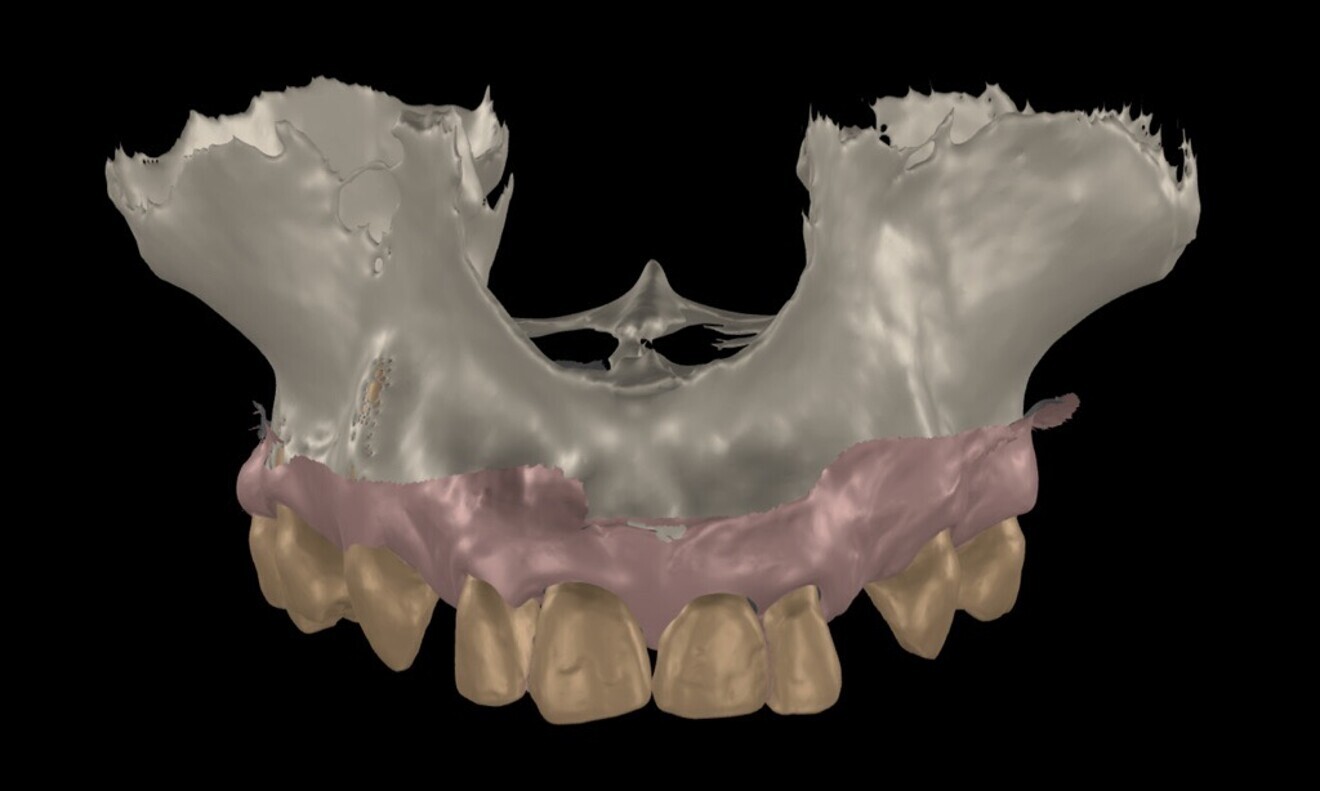

To ensure precise and predictable treatment planning, the DICOM files, STL files and clinical photographs were seamlessly integrated into Smilecloud, utilising advanced artificial intelligence technologies to deliver a highly personalised smile with exceptional precision (Figs. 11–15).

Figs. 11–15: DICOM files, STL files and clinical photographs were integrated into Smilecloud, leveraging artificial intelligence for precise, personalised smile design.